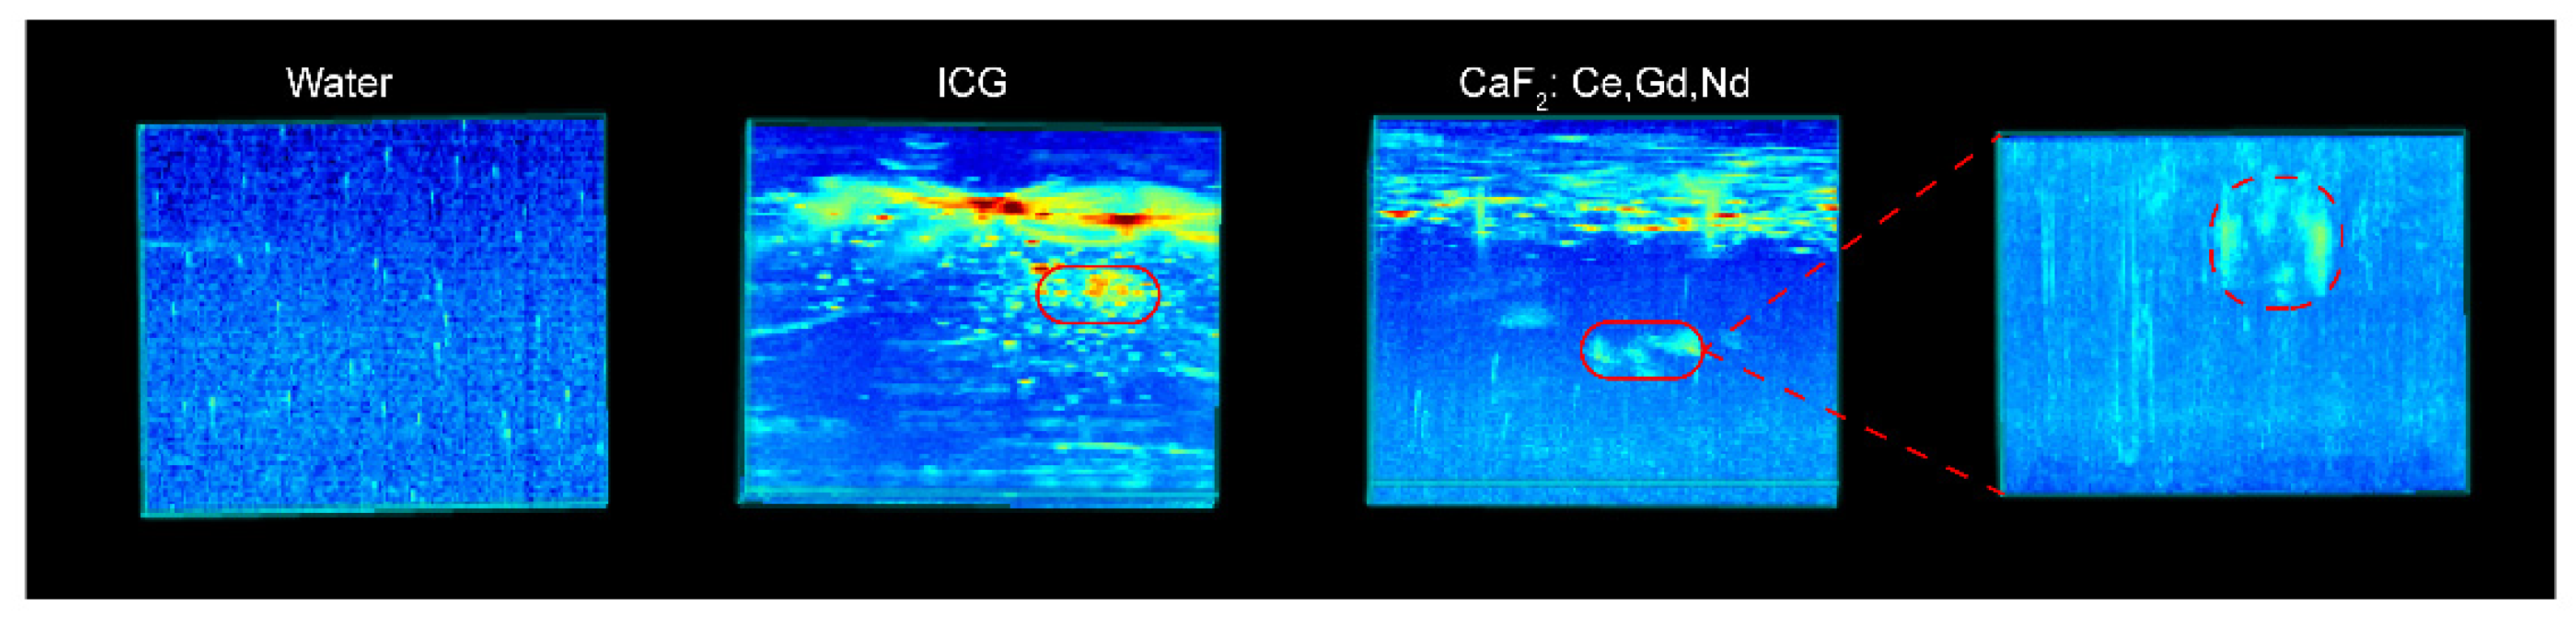

2.9.2. Photoacoustic Imaging